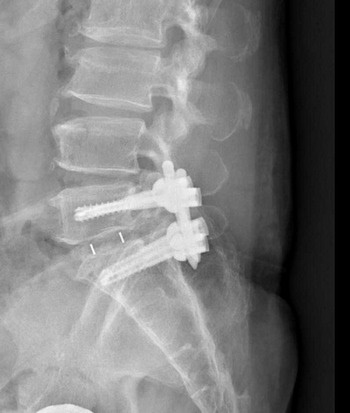

影像檢查顯示,張先生的第五節腰椎椎弓骨折合併脊椎解離。洪祥益主任表示,這類病人多半表現為腰痠背痛、久坐久站困難,通常可先藥物治療觀察,但相較於其他類似問題的病人,張先生疼痛異常明顯,手術中發現脊椎關節內長滿痛風石,這些痛風石如白色黏稠物般,附著在神經與關節縫隙間,若不清乾淨,就會持續引發神經發炎與疼痛,甚至比坐骨神經痛更強烈。團隊透過顯微鏡,在不傷及神經的情況下,仔細將痛風石刮除清理,再以微創固定融合手術完成治療。

右圖:洪祥益主任與團隊透過顯微鏡,在不傷及神經的情況下,仔細將痛風石刮除清理,再以微創固定融合手術完成治療。